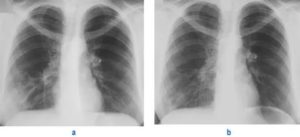

Постановка диагноза производится с использованием инструментальных способов, основным из которых является рентгенография.

При крупозной пневмонии на снимках выявляют усиление легочного рисунка, расширение корня, изменение объема пораженной доли в большую сторону.

При бронхопневмонии отмечается наличие одной или нескольких теней, каждая из которых по размеру не превышает полутора сантиметров. Тени могут сливаться. Рентгенографию проводят в прямой и боковой проекции, что повышает точность исследования.

Дополнительные диагностические манипуляции применяются по необходимости. Рентгенографию проводят всем пациентам без исключения.